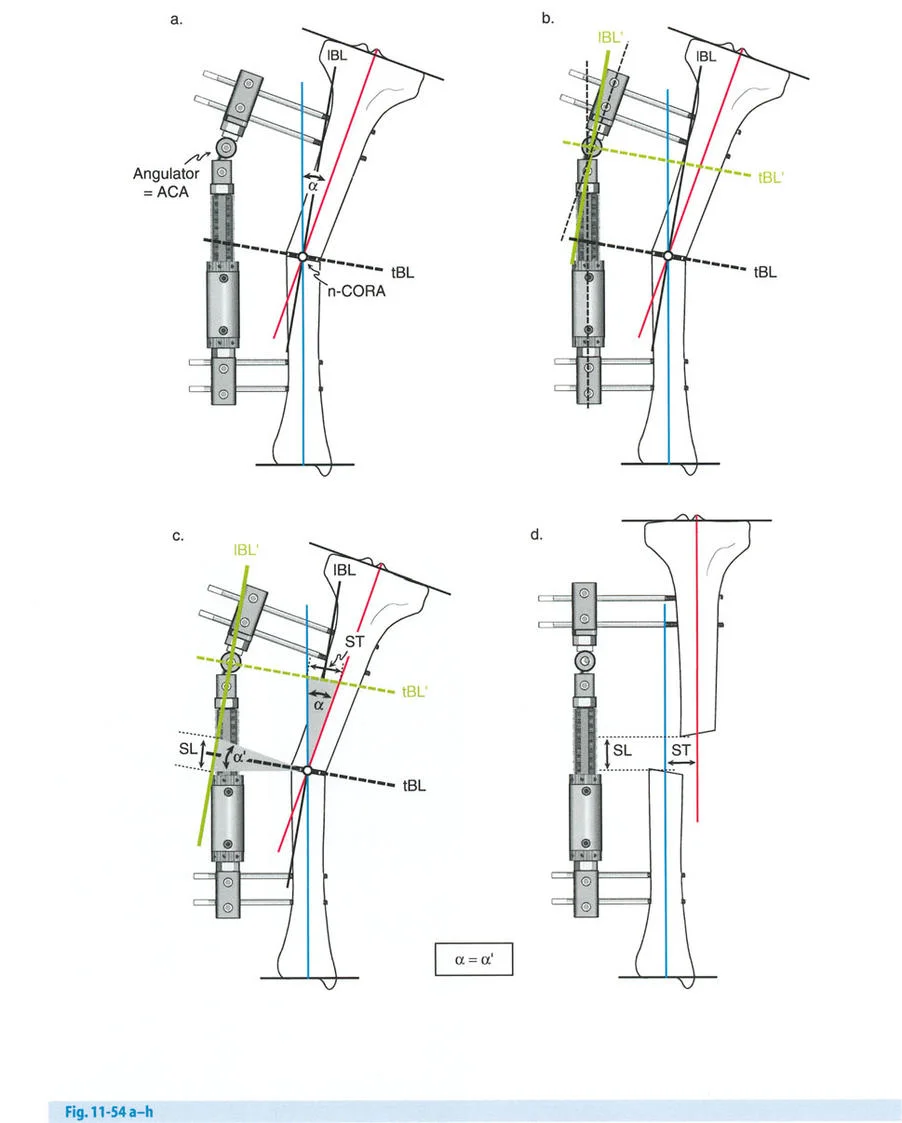

قواعد بالي لقطع العظم (Osteotomy Rules) في وضع الأجهزة

فهم قواعد بالي لقطع العظم أمر لا غنى عنه لتخطيط الإطار:

- قاعدة قطع العظم 1: عندما يمر قطع العظم ومحور تصحيح الانحراف (ACA) كلاهما عبر مركز دوران الانحراف (CORA)، فإن نهايات العظم ستنحرف دون ترجمة (انزياح). يتم استعادة المحور الميكانيكي، وتظل نهايات العظم متقاربة تمامًا، مما يخلق تصحيحًا كلاسيكيًا "إسفينيًا مفتوحًا" أو "إسفينيًا مغلقًا".

- قاعدة قطع العظم 2: عندما يمر محور تصحيح الانحراف (ACA) عبر مركز دوران الانحراف (CORA)، ولكن يتم إجراء قطع العظم على مستوى مختلف (غالبًا بسبب ضعف جودة العظم عند CORA أو مشاكل في الجلد)، فإن نهايات العظم ستنحرف وتخضع لترجمة محسوبة ومقصودة لإعادة محاذاة المحور الميكانيكي.

- قاعدة قطع العظم 3: (للاكمال) عندما يمر قطع العظم عبر مركز دوران الانحراف (CORA)، ولكن يتم وضع محور تصحيح الانحراف (ACA) خارج CORA، سيتم إنشاء تشوه ترجمة جديد، وهو خطأ شائع في وضع المفصلات غير المخطط له جيدًا.

في المنشآت القريبة من المفصل، غالبًا ما نعتمد على قاعدة قطع العظم 2. نظرًا لأنه لا يمكننا قطع العظم بأمان عند خط المفصل تمامًا (مركز دوران الانحراف CORA)، فإننا نقطع العظم في مستوى أدنى في منطقة الميتافيسيس. بعد تحقيق التصحيح الزاوي عبر المفصلات (محور تصحيح الانحراف ACA)، يتم إعادة محاذاة خطوط المحور الميكانيكي بشكل مثالي، ولكن نهايات العظم في موقع قطع العظم تتحرك بالنسبة لبعضها البعض.

إتقان معدلات الشد: قاعدة المثلثات المتشابهة

القاعدة الذهبية البيولوجية لتوليد العظم بالشد، التي وضعها إليزاروف بعد عقود من التجارب على الحيوانات والبشر، هي معدل شد يبلغ 1 ملم يوميًا. يتم تقسيم هذا عادة إلى زيادات قدرها 0.25 ملم كل 6 ساعات لمحاكاة النمو المستمر للوحة النمو.

ومع ذلك، فإن الخطأ الشائع، الذي قد يكون كارثيًا أحيانًا للجراحين المبتدئين، هو سوء فهم أين يجب أن يحدث هذا الـ 1 ملم يوميًا.

معدل 1 ملم/يوم ينطبق بشكل صارم على القشرة المقعرة للعظم في موقع قطع العظم (الحافة الأمامية للإسفين المفتوح). نظرًا لأن الجهاز (قضيب الشد أو دعامة TSF) يقع على مسافة من العظم، خارج غلاف الأنسجة الرخوة، فإنه يتحرك على طول قوس أكبر بكثير. إذا وجهت المريض لشد القضيب بمعدل 1 ملم يوميًا، فإن العظم الفعلي سيُشد بجزء ضئيل من هذا المعدل، مما يؤدي إلى التصلب المبكر لموقع قطع العظم.

حساب معدل الشد الحقيقي

لحساب المعدل الصحيح للشد عند المفصلة، نستخدم قاعدة المثلثات المتشابهة، والتي تعتمد أساسًا على القاعدة الهندسية للدوائر متحدة